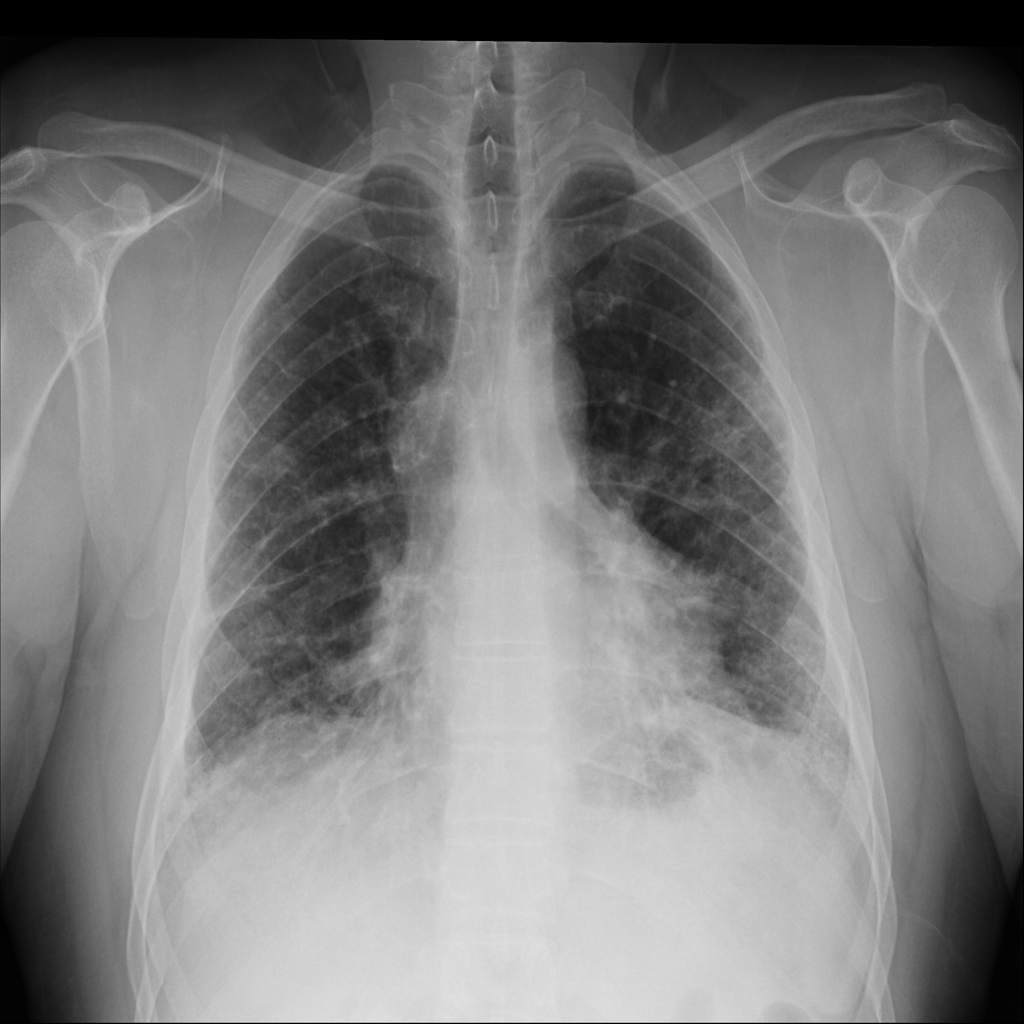

PAT-C77C · IMG-003Fibrosis

PAT-C77C · IMG-003

PA